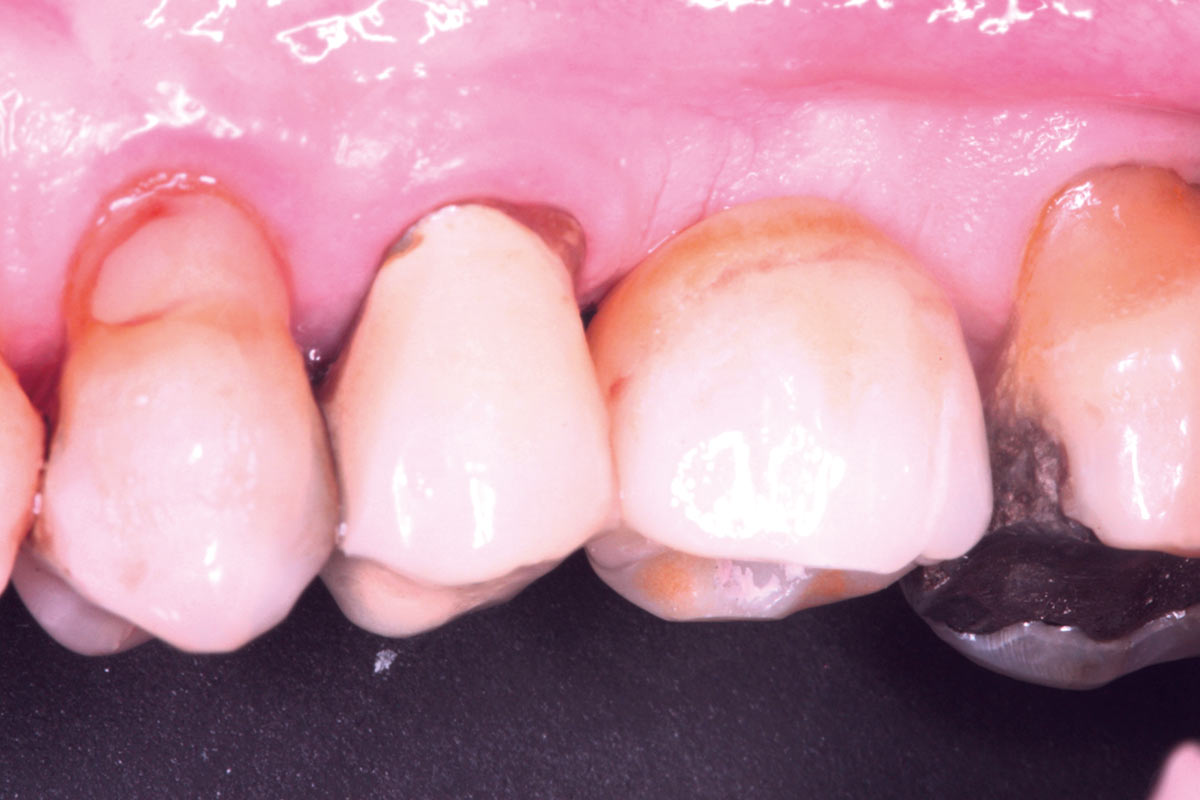

30/35 - Peri-implant tissues at 3 weeks from the second stageMaxillary sinus cyst removal using the Crocodile Technique and subsequent lateral sinus lift - Dres. C. Scognamiglio and A. Perucchi

31/35 - Peri-implant tissues at 3 weeks from the second stageMaxillary sinus cyst removal using the Crocodile Technique and subsequent lateral sinus lift - Dres. C. Scognamiglio and A. Perucchi